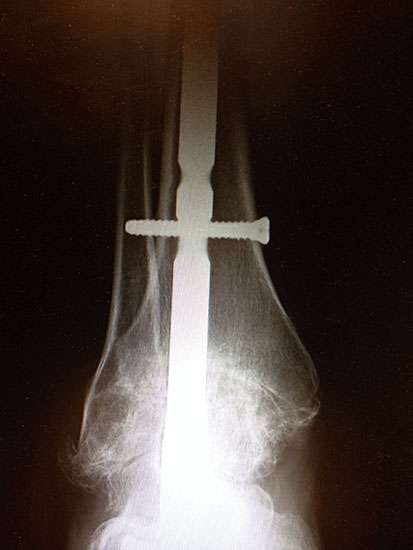

Bei schweren Fehlstellungen, Band-Instabilitäten oder ausgedehnten Defektsituationen (z.B. nach Endoprothesenausbau) oder begleitender Arthrose des unteren Sprunggelenks kann nach Zubereitung des OSG eine retrograde Nadelarthrodese durchgeführt werden (Abb. 10 a – c). Wird das untere Sprunggelenk in die Arthrodese einbezogen, so ist der Rückfuß wesentlich rigider, so dass wenn möglich das untere Sprunggelenk erhalten werden sollte.

Abbildung 10a

Abbildung 10b

Abbildung 10c

Abbildung 10d